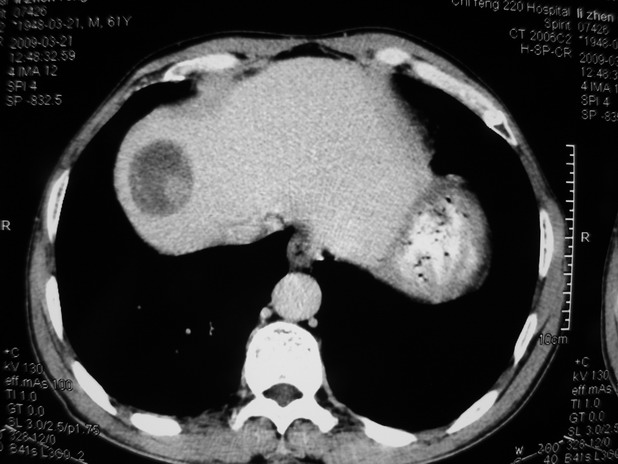

以下是引用余辉在2009-3-21 21:36:00的发言:[br]图像太乱了,建议楼主直接将强化数据按顺序列出来,病灶位置较表浅薄,有肝炎病史,灶内实性成分有显著强化,动脉期约60hu,考虑肝癌可能性大,进一步检查。